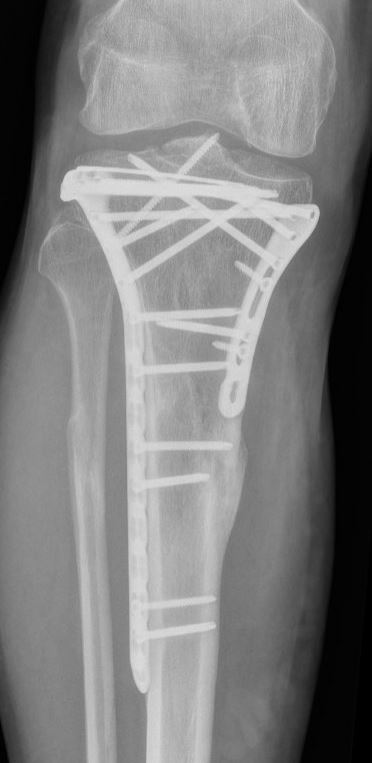

Operatie

Indien u geopereerd moet worden, zal dat meestal gebeuren met een plaat en schroeven om de breukdelen stevig aan elkaar vast te zetten en te verbinden aan de rest van het scheenbeen. Soms zijn hiervoor zelfs meerdere platen nodig. In een enkel geval is het gebruik van alleen schroeven voldoende. Welke operatie u precies krijgt, is afhankelijk van de eigenschappen van de breuk, de toestand van de huid, spieren, zenuwen en bloedvaten en de voorkeur van uw traumachirurg.